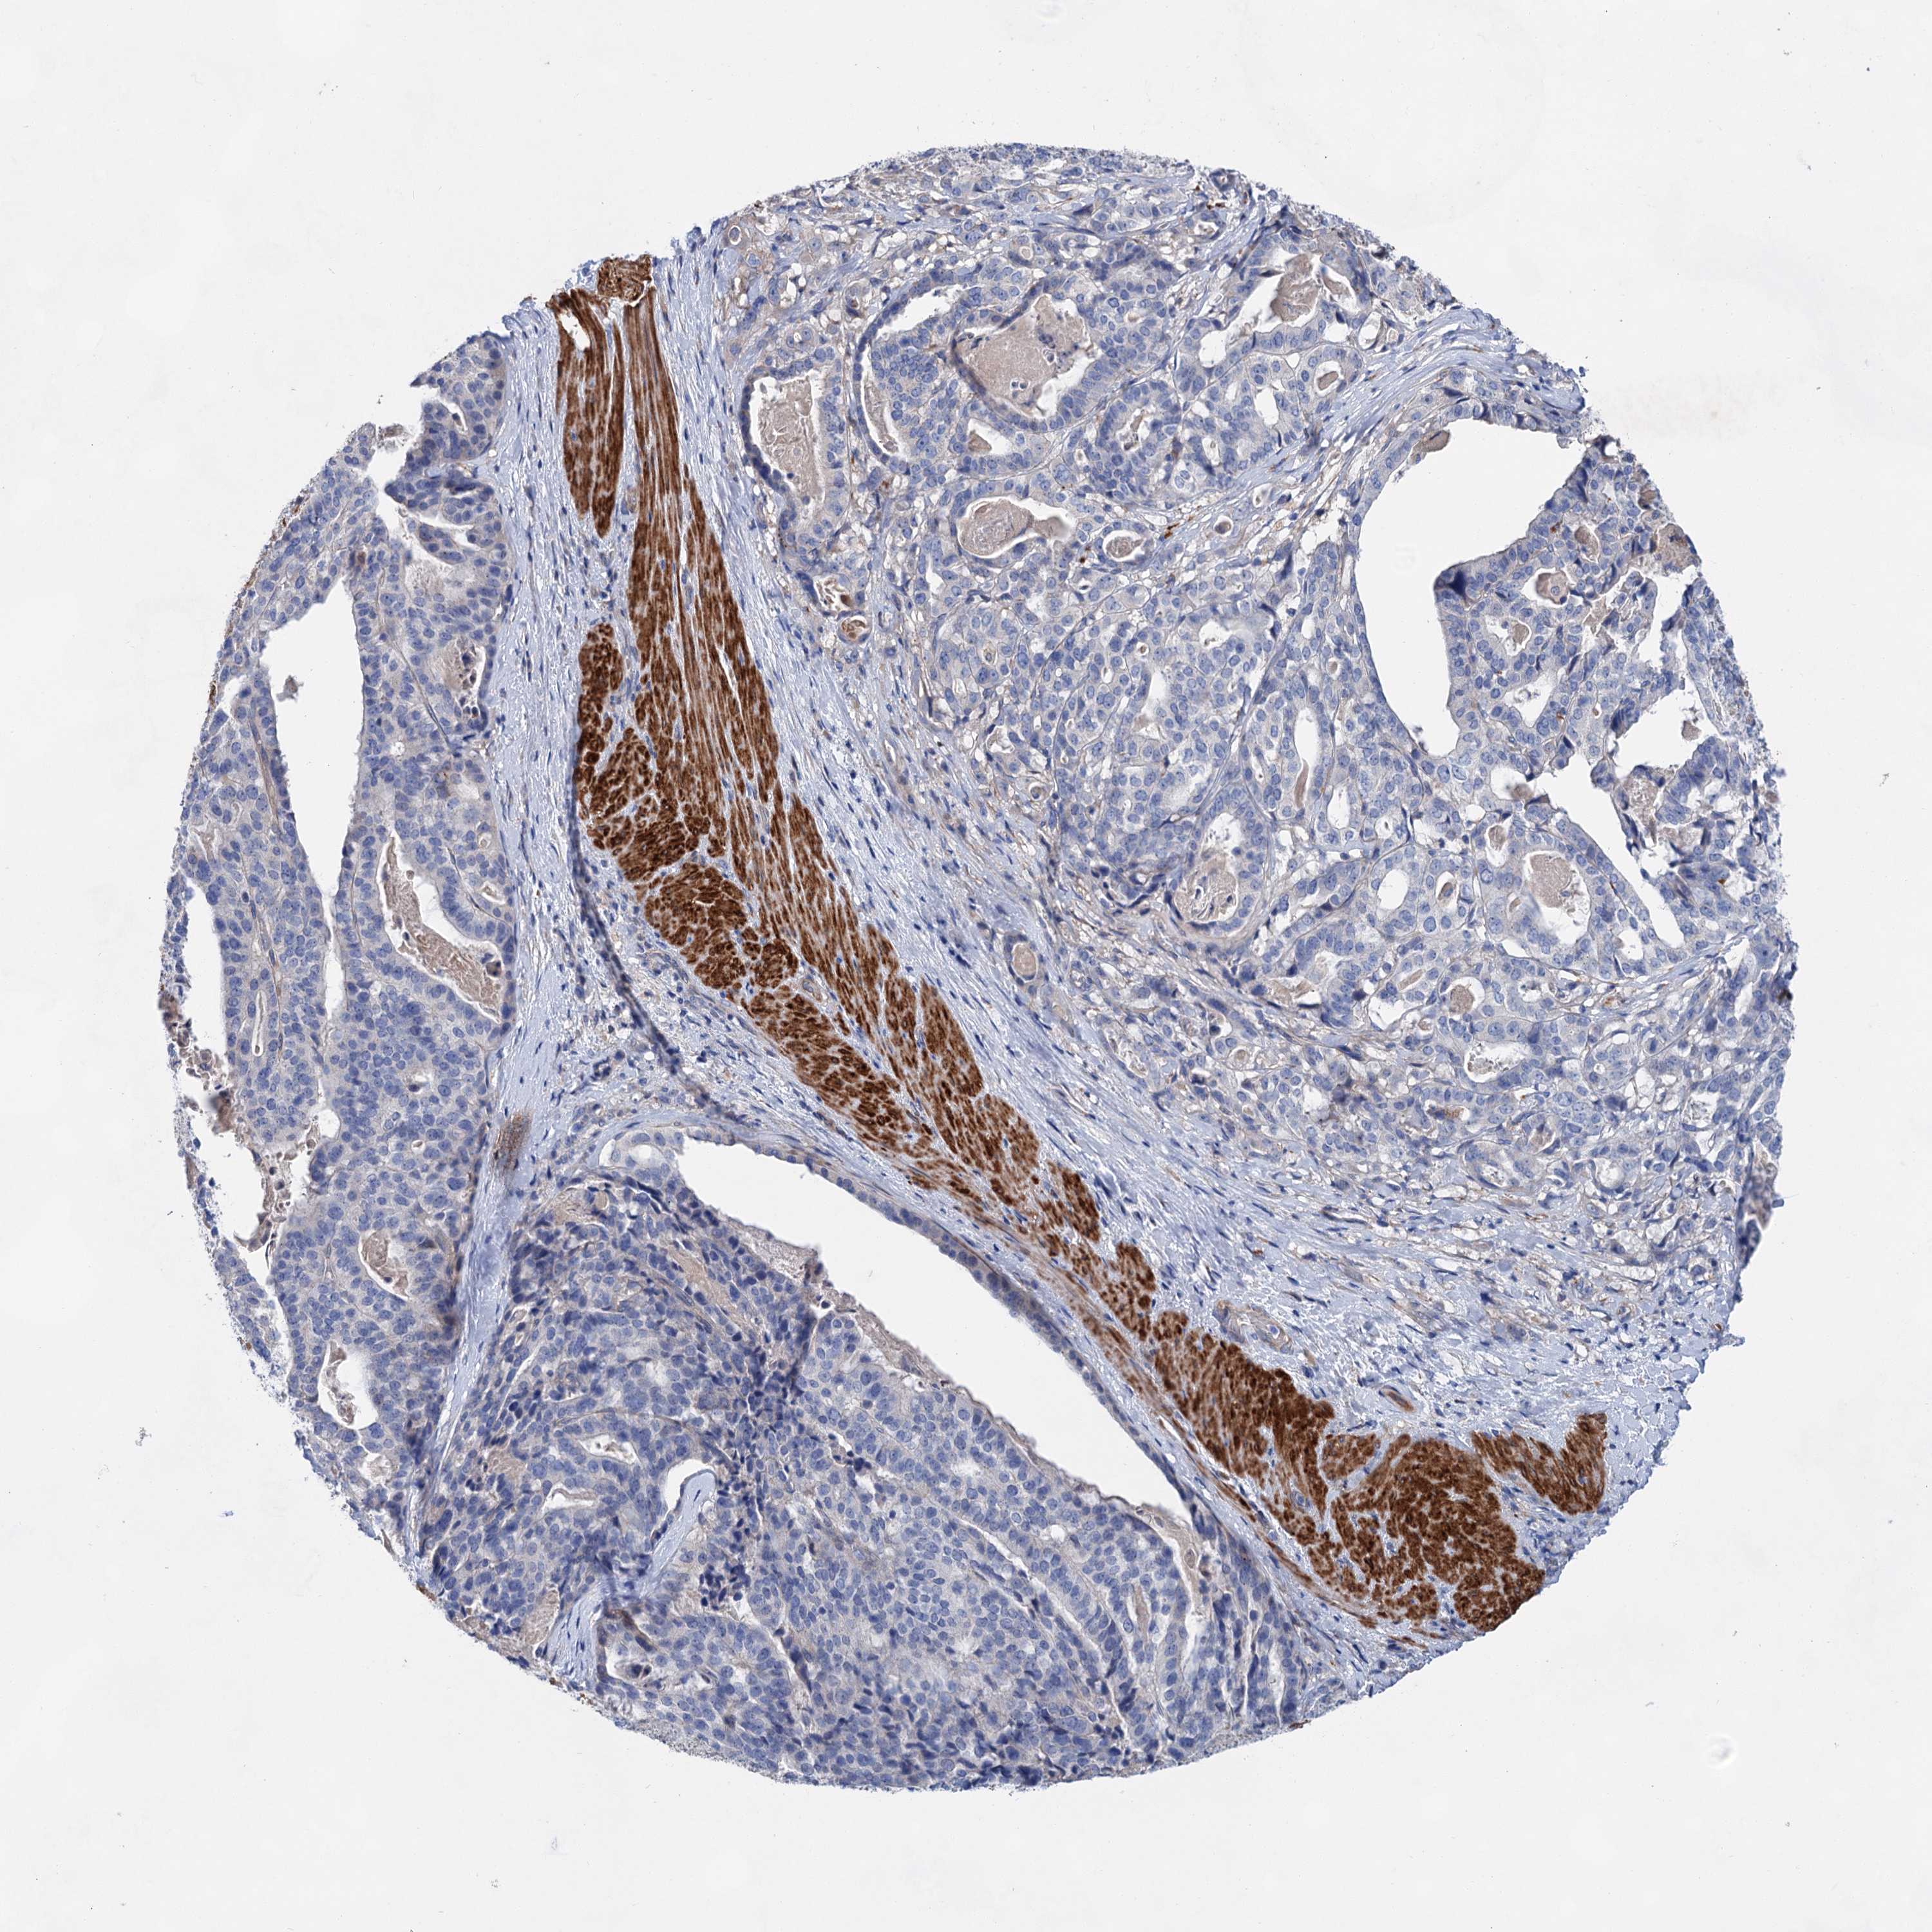

STOMACH CANCER - Protein expressioni

A mouse-over function shows sample information and annotation data. Click on an image to view it in a full screen mode. Samples can be filtered based on level of antibody staining by selecting one or several of the following categories: high, medium, low and not detected. The assay and annotation is described here.

Antibody stainingi

Antibody staining in the annotated cell types in the current human tissue is reported as not detected, low, medium, or high, based on conventional immunohistochemistry profiling in selected tissues. This score is based on the combination of the staining intensity and fraction of stained cells.

Each image is clickable and will lead to virtual microscopy that enables deeper exploration of all samples and also displays staining intensity scores, fraction scores and subcellular localization as well as patient and tissue information for each sample.

Antibody HPA036159

Antibody HPA057384

Staining

High

Medium

Low

Not detected

Intensity

Strong

Moderate

Weak

Negative

Quantity

>75%

75%-25%

<25%

None

Location

Nuclear

Cytoplasmic/membranous

Cytoplasmic/membranous,nuclear

Adenocarcinoma, NOS

Adenocarcinoma, High grade